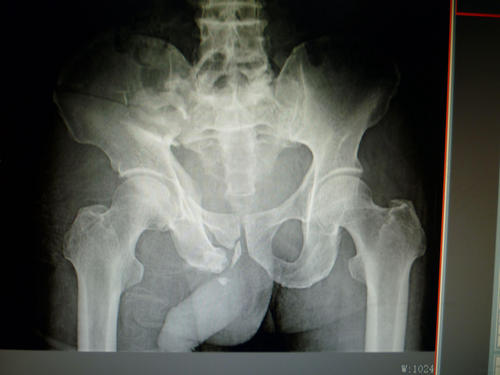

骨盆出现粉碎性骨折的患者要尽快去医院拍片检查,通过检查医生会对病症做系统的评估,判断骨折的轻重程度,再对症治疗。一般如果是轻微的局部粉碎性骨折,只需要对骨折部位进行对位对线治疗,防止骨折部位发生移位,并进行系列保守治疗就可以了,治疗期间患者要尽量卧床休息,并固定好骨盆,这样才有助于骨盆的愈合。